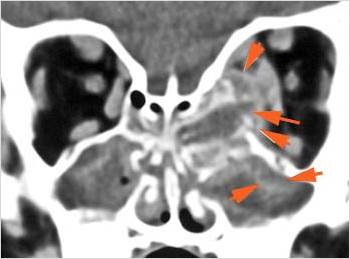

Sinuses

There is soft tissue swelling anterior to the frontal sinus or in the soft tissues surrounding the maxillary sinuses. [Yes/No]

There is mucoperiosteal thickening in the sinuses. [Yes/No]

There is mucosal enhancement in the sinuses. [Yes/No]

There is an air fluid level in the frontal sinus. [Yes/No]

There is bone erosion along the walls of any affected sinuses. [Yes/No]

There is an appearance of bone expansion, due to regressive remodeling and suggestive of pre-existing mucocele, along the walls of any affected sinuses. [Yes/No]